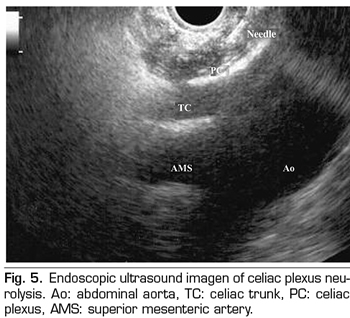

Endoscopic ultrasound offers the advantage of larger visualization of the celiac plexus at a short proximity, allowing larger precision and safety in the administration of the neurolytic agent and avoiding injection into vascular structures through the use of Doppler (37) (Figure 5). However, the studies supporting endoscopic ultrasound neurolysis, considered similarly to percutaneous technique as a rescue therapy, are limited to retrospective uncontrolled studies (38). Pauli et al. published a meta-analysis that concludes that this technique achieves an 80% pain reduction in patients with pancreatic cancer (39). Some studies show a slight decrease in opioid consumption, but without strong scientific evidence.

Regarding adverse effects, they are reported in a limited series of retrospective publications and case series, being hypotension (11%), diarrhea (18%), and transient abdominal pain (1.5 to 8%) described (37). Theoretically, this technique is safer, with its anterior approach through the gastric wall and direct passage of the needle to the plexus visualizing the vessels, without having to cross the retrocrural space (41). Even so, fatal complications have also been published with this technique. Gimeno-García et al. (42) described the first complication of thrombosis and vasospasm of the celiac artery that produced a multiorganic ischemia and the death of the patient. Since then, this complication has been published in 2 other studies, which also ended in death (43,44). Other adverse effects described are retroperitoneal bleeding and 2 cases of paraplegia.

Among the contraindications related to this technique the following are found: the presence of gastric or esophageal varix - since they increase the risk of bleeding-, an unstructured anatomy, direct tumor invasion of the plexus, and congenital malformations of the celiac trunk or of the superior mesenteric artery.